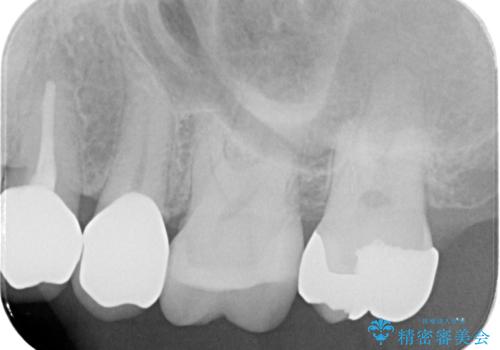

銀歯を除去し隣の歯も虫歯が見られたのでジルコニアクラウン、e-maxインレーで治療を行いました。

適合の良い被せ物、詰め物が入りました。